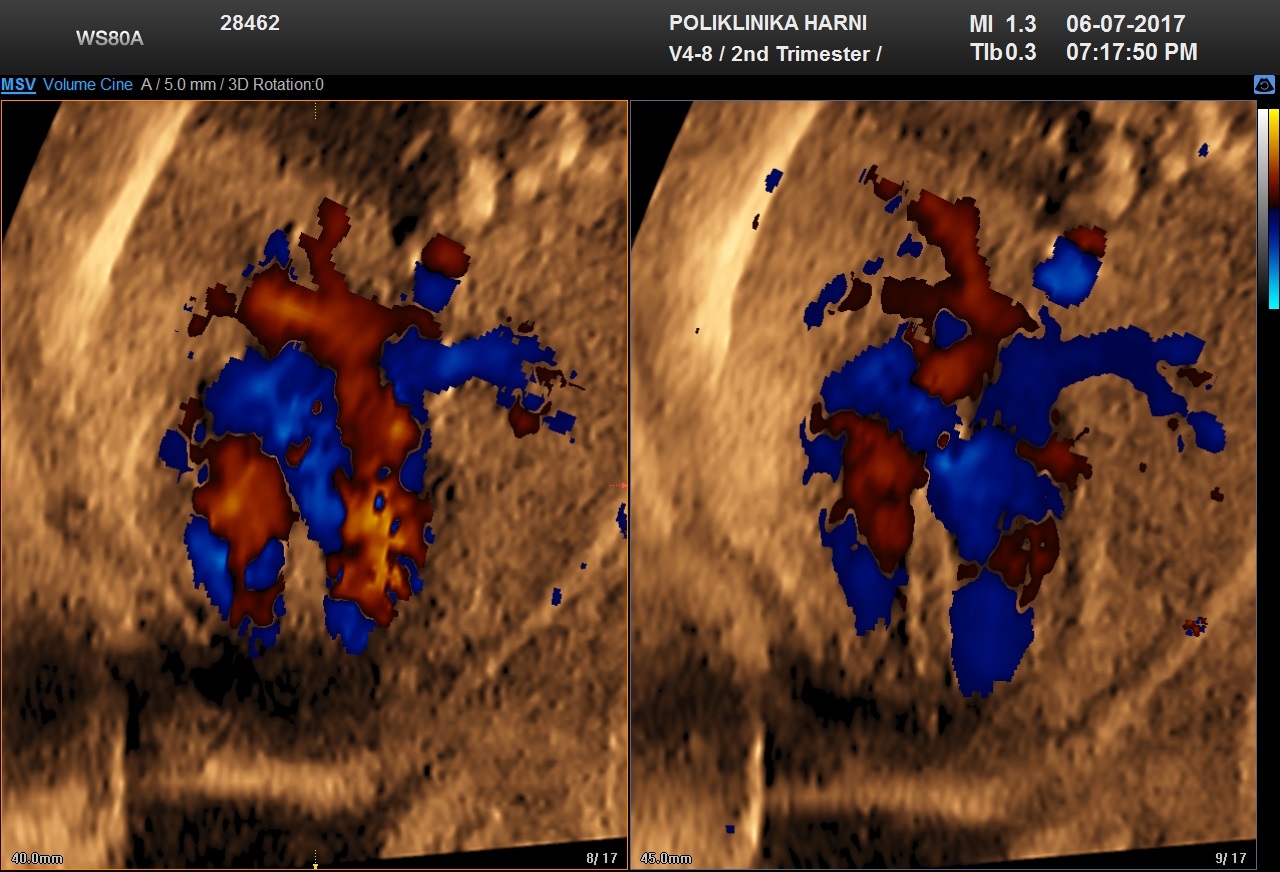

Duktus venozus krvna je žila koja nastaje u 6. tjednu trudnoće nakon obliteracije kompletne desne umbilikalne vene, kranijalnog dijela lijeve umbilikalne vene, lijeve žumanjčane vene i dijela jetrenih anastomoza. Ova krvna žila postaje poveznica - shunt između lijeve umbilikalne vene i desnog hepatokardinalnog kanala. Protok kroz duktus venozus ima karakterističnu krivulju na doplerskom sonogramu: prvi val je brzi pozitivni protok za vrijeme sistole ventrikula, drugi je nešto manje brzine za vrijeme dijastole ventrikula, a treći je i dalje pozitivan protok tijekom atrijske kontrakcije. Ultrazvučno možemo prepoznati povećani otpor u duktusu venozusu kao i izostanak dijastoličkog protoka ili povratni protok u vrijeme kontrakcije atrija, te veće razlike između sistole i dijastole.

S obzirom da protok u duktusu venozusu predstavlja izravni gradijent tlakova između umbilikalne vene i desne pretklijetke, dodatno se može prepoznati i izostanak dijastole te povratni protok u donjoj šupljoj veni i pulsacije u umbilikalnoj veni, koje odgovaraju kontrakciji atrija. Sukladno teorijama o razvitku nakupljanja tekućine u nuhalnoj regiji, poremećaj priljeva / preload i odljeva / afterload može nastati zbog prevelikog opterećenja zbog dotoka povećanih količina cirkulirajućih tjelesnih tekućina, ali isto tako i zbog poremećenog protoka, odnosno propustljivosti krvi kroz srce u fetusa sa zastojnim srčanim greškama. Oba stanja dovode do venskog zastoja i povišenog otpora koji prepoznajemo po povratnom protoku u duktusu venozusu već u prvom tromjesečju. Takav nalaz između 11.- 14. tjedna povezan je s kromosomopatijama, anomalijama srca i lošim ishodom trudnoće.

Nedostatak protoka / zero flow ili absent flow ili negativan protok / inversed flow u duktusu venozusu tijekom atrijske kontrakcije nalazi se u 80% fetusa s kromosomskim abnormalnostima, uz oko 5% fetusa s normalnim kariogramom. Kako nije dokazana veza između patološkog protoka u ductusu venosusu i povećanog nuhalnog nabora, paralelno ispitivanje oba faktora povisuje stopu detekcije trisomije 21 na 94%. Otuda je pregled protoka kroz duktus venozus tehnikom obojenog Dopplera sastavni dio svakog ozbiljnijeg traganja za ultrazvučnim biljezima kromosomopatija.